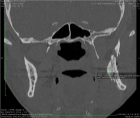

Sagittal split osteotomy (SSO) of the mandible is still an important part of orthognathic surgery, but “bad split” fractures that happen during the surgery are still a big problem. This report describes a rare case of bilateral bad split associated with highly compact mandibular bone (D1–D2 type) in a 53-year-old male undergoing mandibular advancement. The bone was too hard for the piezoelectric and rotary tools to work, and there was very little bleeding. This caused fractures in the cortex and lingual. Postoperative computed tomography confirmed the presence of highly dense bone, correlated with delayed healing and recurrence. Consistent pre-surgical CT scanning for an assessment of the density of the mandibular bone can provide essential information about the potential risk of the osteotomy procedure in the patient. Performing a careful bone quality and density examination pre-operatively will allow the surgeons to select the most appropriate instruments and surgical techniques that will fit the patient’s individual anatomy. Such a point escalates to being very significant when dealing with the geriatric population, as bone density increase can not only alter the fracture behavior but also the recovery process during and after surgery. The inclusion of regular CT-based bone density evaluations into the preoperative routine not only facilitates the anticipation of surgical difficulties but also results in safer and more efficient osteotomies.